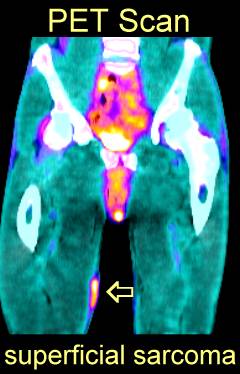

Patient with a large sarcoma in the right anterior thigh: CT here, MRI here and here, PET after neoadjuvant chemotherapy here and here

PET Scan